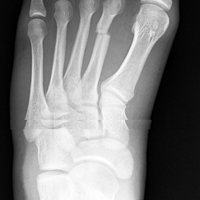

Fractura de 2 metatarso con un poquito de desplazamiento, es necesario que el hueso esté completamente alineado para sanar?